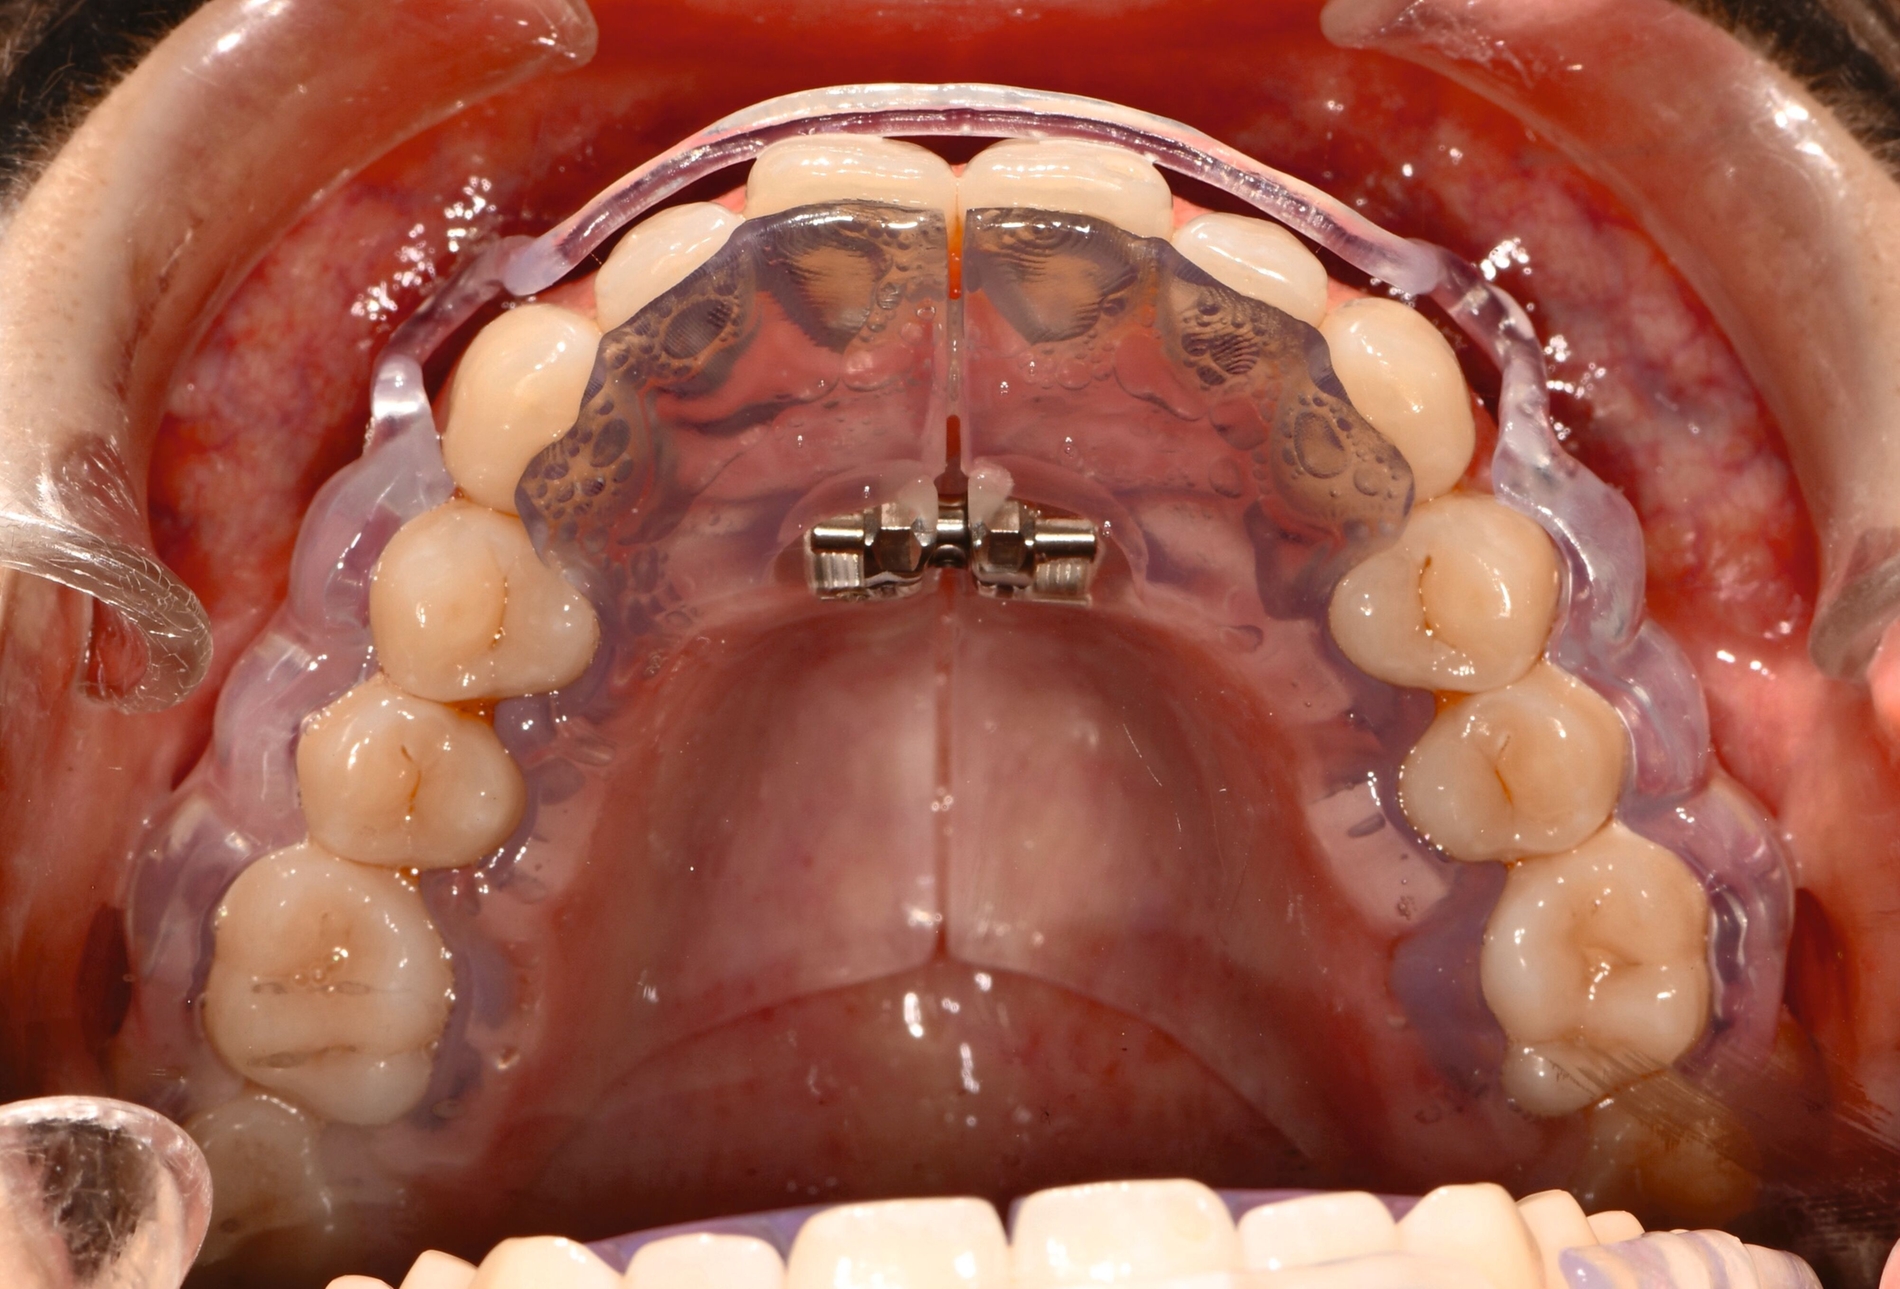

Herausnehmbare Apparaturen

Als hochinnovatives Feld hat sich auch die Herstellung herausnehmbarer Apparaturen im 3-D-Druck entwickelt (Abbildung 4), beschränkt sich jedoch noch auf einzelne Forschungsansätze [Al Mortadi et al., 2012; van der Meer et al., 2016; Graf et al., 2022; Keller et al., 2022]. Intensiv an neuen Konzepten in der Herstellung 3-D-gedruckter herausnehmbarer Apparaturen wird am Universitätsklinikum Heidelberg geforscht. Da herausnehmbare kieferorthopädische Apparaturen im Regelfall bei jungen Patienten eingesetzt werden, kommt dem Vorteil einer unbegrenzten Replikation und einer kostengünstigen und schnelleren Herstellung ein besonderer Stellenwert zu.

Im Unterschied zu konventionellen Apparaturen bestehen die 3-D-gedruckten Apparaturen vollkommen aus Kunststoff. Eine Einarbeitung metallischer Elemente nach dem 3-D-Druck ist möglich [Al Mortadi et al., 2012; Al Mortadi et al., 2024], erfordert jedoch zusätzlichen Zeitaufwand. Zur Herstellung herausnehmbarer Apparaturen eignen sich konventionelle praxisinterne 3-D-Stereolithografie-Drucker, die in vielen Fällen bereits im regulären Praxisalltag zum Modelldruck verwendet werden. Die verwendeten Kunststoffe sollten dabei eine Klasse-IIa-Zertifizierung aufweisen, so dass ein sicherer langfristiger intraoraler Einsatz der Apparatur gewährleistet ist. Weiter muss die Apparatur nach dem 3-D-Druck gemäß den Herstellerangaben nachprozessiert werden. Im Regelfall beinhaltet dieser Prozess ein Waschen in Isopropylalkohol (IPA) sowie eine Nachhärtung im Lichthärtegerät. Eigens durchgeführte Studien sowie die bisherige klinische Erfahrung bestätigen eine hohe mechanische Stabilität, eine hohe Passgenauigkeit sowie eine breite Akzeptanz der Patienten [Roser et al., 2021; Roser et al., 2023; Segnini et al., 2023]. Des Weiteren wecken die 3-D-gedruckten Apparaturen bei den meist jungen Patienten großes Interesse, was wiederum die Trage-Compliance unterstützt. Durch weitere Entwicklungen im 3-D-Druckbereich wird zukünftig auch ein Farbdruck möglich werden.